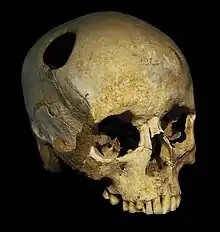

The perimeter of the hole in this trepanated Neolithic skull is rounded off by ingrowth of new bony tissue, indicating that the patient survived the operation.

The perimeter of the hole in this trepanated Neolithic skull is rounded off by ingrowth of new bony tissue, indicating that the patient survived the operation. Skulls from the Bronze Age, exposed at the Musée archéologique de Saint-Raphaël (Archeological Museum of Saint-Raphaël), found in Comps-sur-Artuby (France). The subjects survived operations.